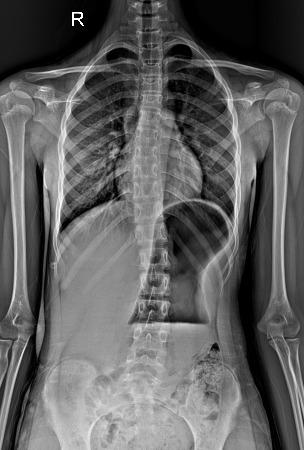

一年前,小圆父母察觉到孩子异常——耸肩驼背、双肩与腰部明显不对称。最初以为是学业负担重所致,但症状持续未见好转。今年4月,家人带她前往常德市第一中医医院求诊。检查结果令人揪心:脊柱全长片清晰显示其胸椎向右弯、腰椎向左弯,形成典型“S”形,胸椎4-10节及胸11至腰4节Cobb角分别达14°与25°,脊柱柔韧性为75%。

令人欣喜的是,在门诊完成10次PSSE训练并坚持居家锻炼后,小圆3个月后复查显示疗效显著——胸椎Cobb角降至6°,腰段Cobb角大幅收窄至15%,侧弯外观明显改善。